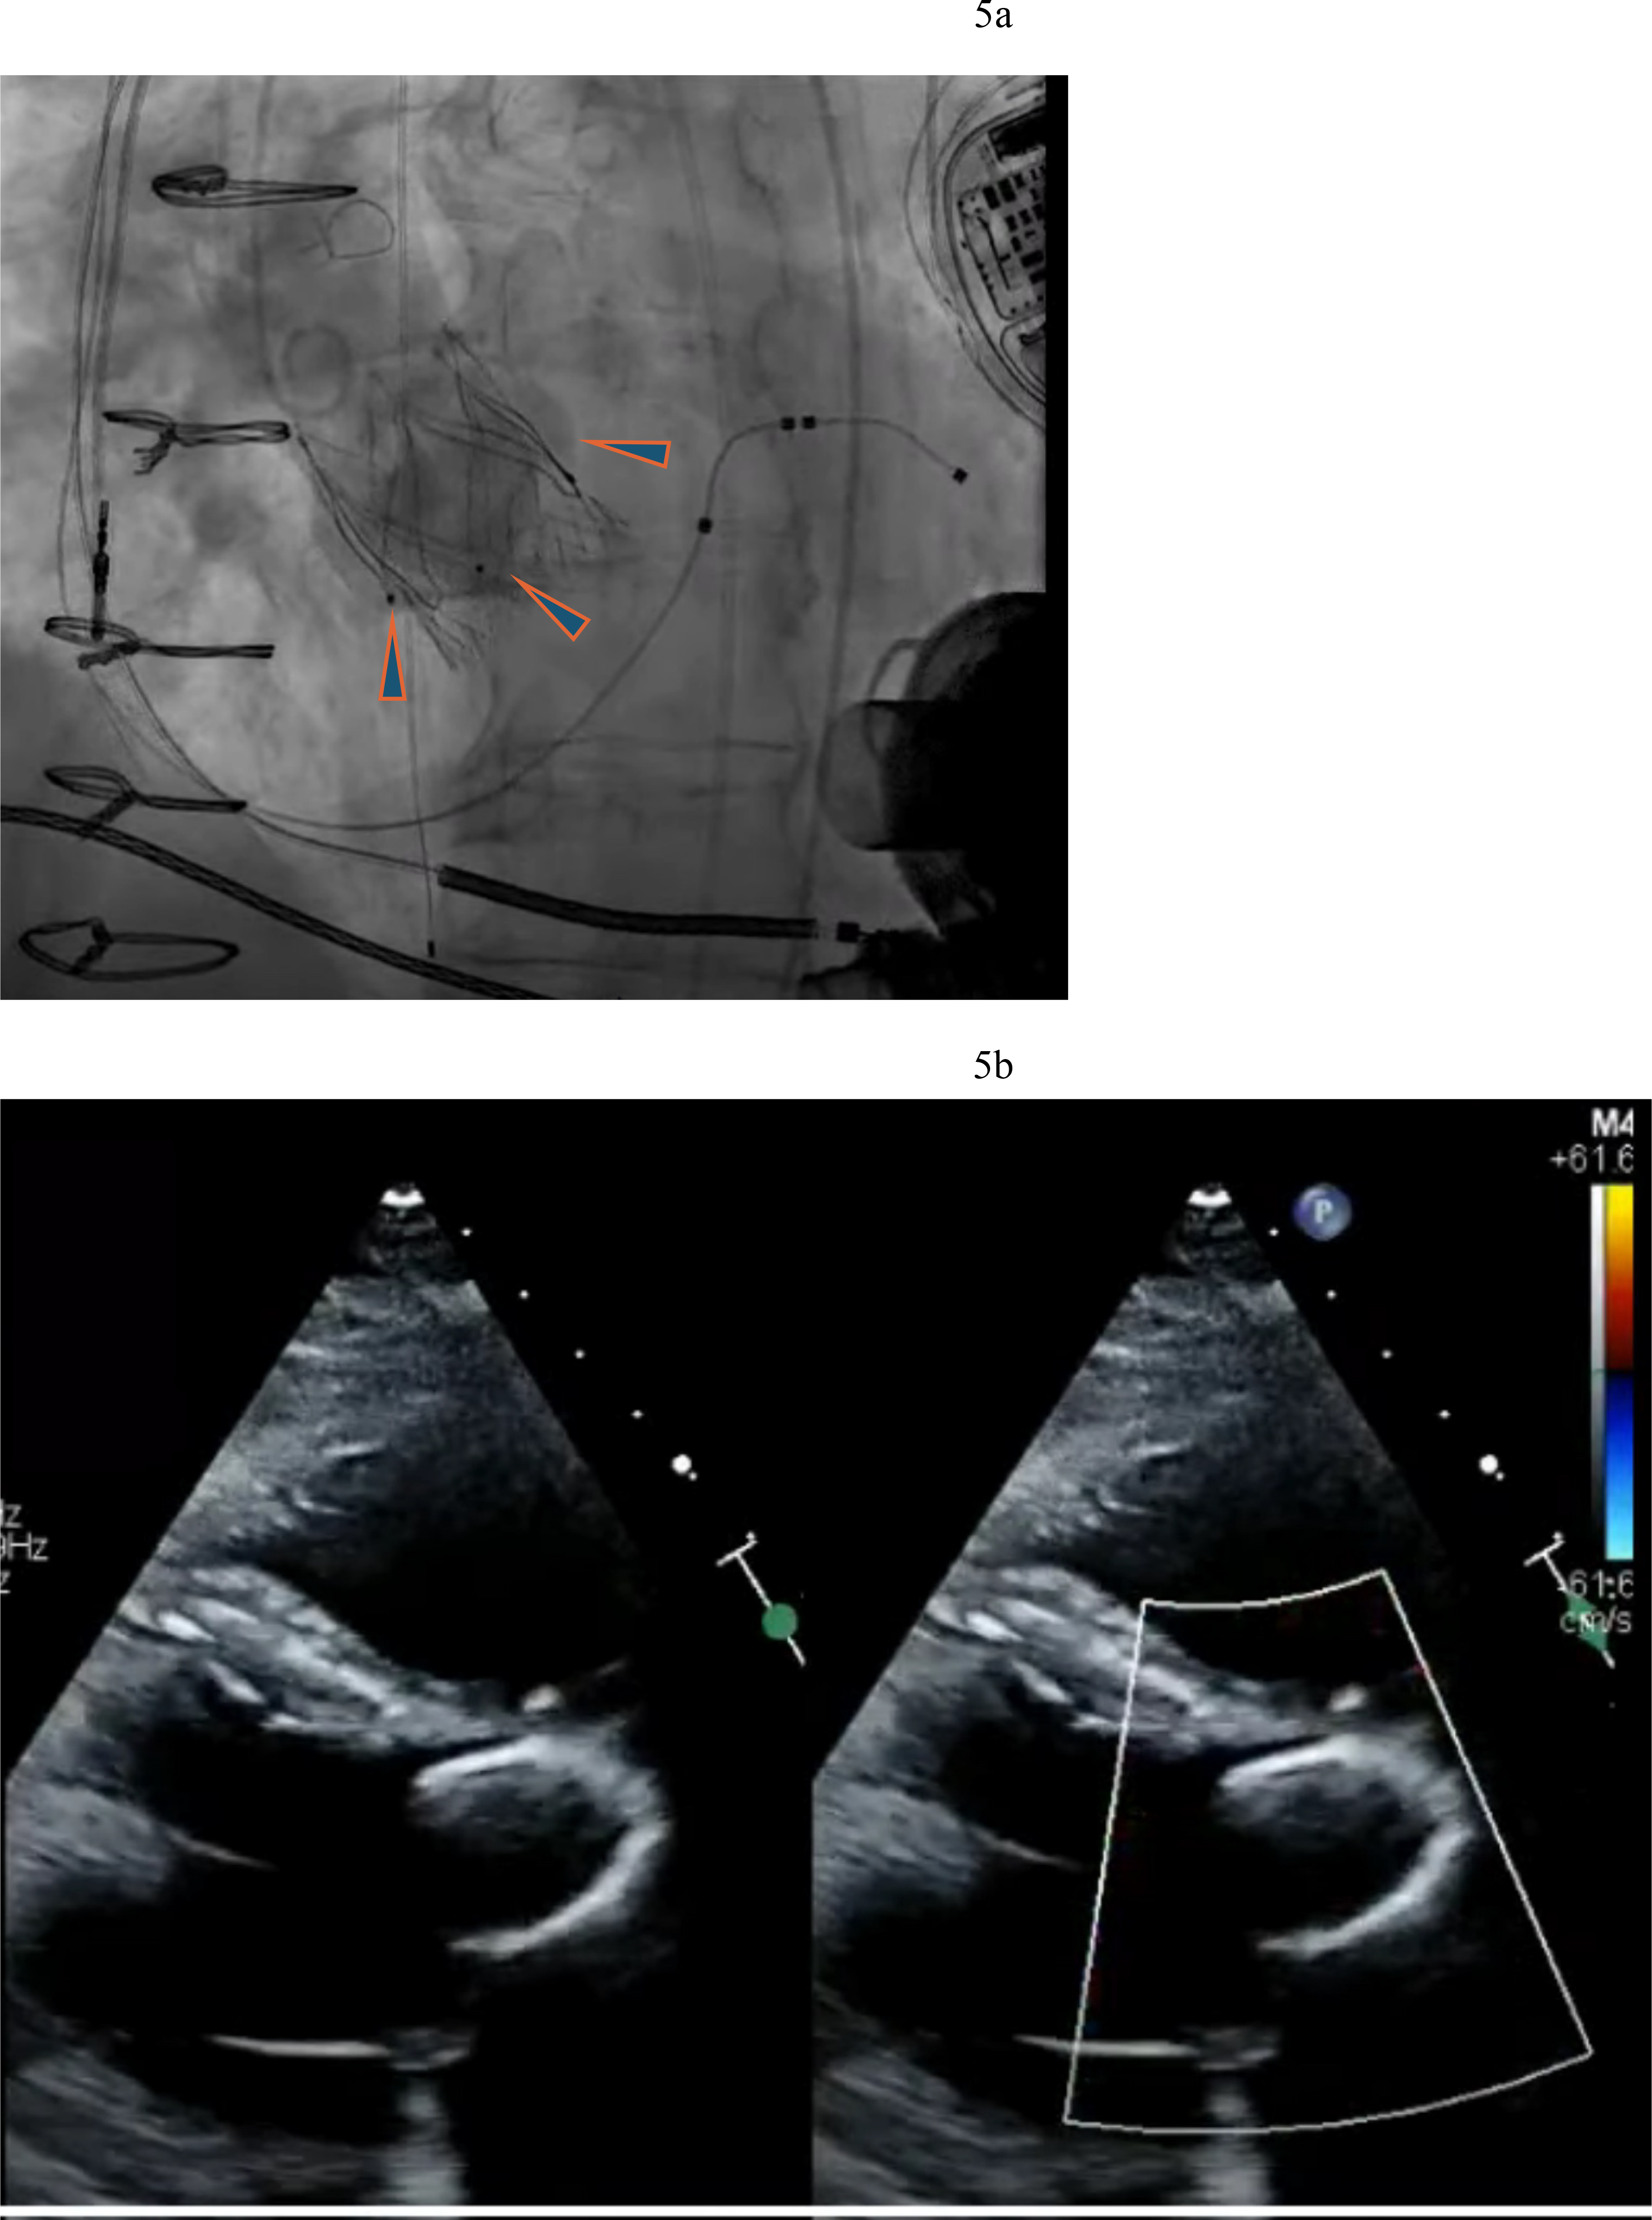

The emergence of dedicated devices for aortic regurgitation which rely on leaflet capture for device fixation (JenaValve and J-Valve) has the potential to address this unmet clinical need. The JenaValve (JenaValve Technology, Inc., Irvine, California, USA) is the only currently available device with CE mark for the treatment of aortic regurgitation. It is currently under investigation in the USA. The JenaValve is a porcine pericardial valve on a self-expanding nitinol frame made of three integrated arms called locators. The locators align the valve with the native aortic valve native aortic valve anatomy and clip onto the native leaflets providing fixation independent of valve calcification. Ranard et al. [19] recently reported the first use of the JenaValve to address severe aortic regurgitation in a LVAD patient. We have utilized the Jena-Valve platform in LVAD patients with technical success and excellent clinical results (Fig. 5a,b).

Fig. 5. Jena-Valve in LVAD patient with severe AR. (a) Jenavalve 27 mm with three locators (arrowheads) anchored to the aortic valve. (b) Resolution of AR after Jenavalve implantation.